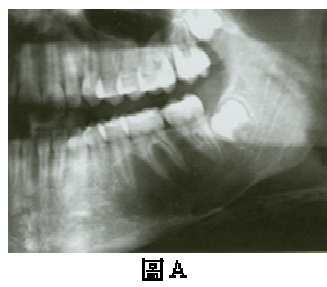

76. 一位16歲男孩在常規X光檢查時,發現左下顎臼齒下方有一放射線透性影像,牙根之間呈現扇形(scalloped),病灶下緣周界較不 清晰(圖A),根尖片可見到清晰之齒槽骨板(lamina dura)(圖B),患處牙齒之牙髓均呈活性反應,口外醫師安排活體切片檢查 時發現放射線透性(radiolucent)病灶內空無一物,刮取病灶周邊組織鏡檢(圖C),可見鄰近之骨組織有一薄層含血管之結締組 織,並沒有發現任何上皮襯底(epithelial lining)。您認為下列何者較符合上述之診斷?

(A)動脈瘤性骨囊腫(aneurysmal bone cyst) (B)史塔尼氏囊腫(Stafne bone cyst) (C)單純性骨囊腫(simple bone cyst) (D)齒源性角化囊腫(odontogenic keratocyst)